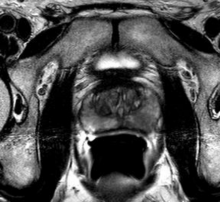

Urologists at Rush University Medical Center are the first in Chicago to offer a powerful new tool for visualizing and monitoring the prostate in men who have high prostate-specific antigen (PSA) levels and in detecting prostate cancer more accurately.